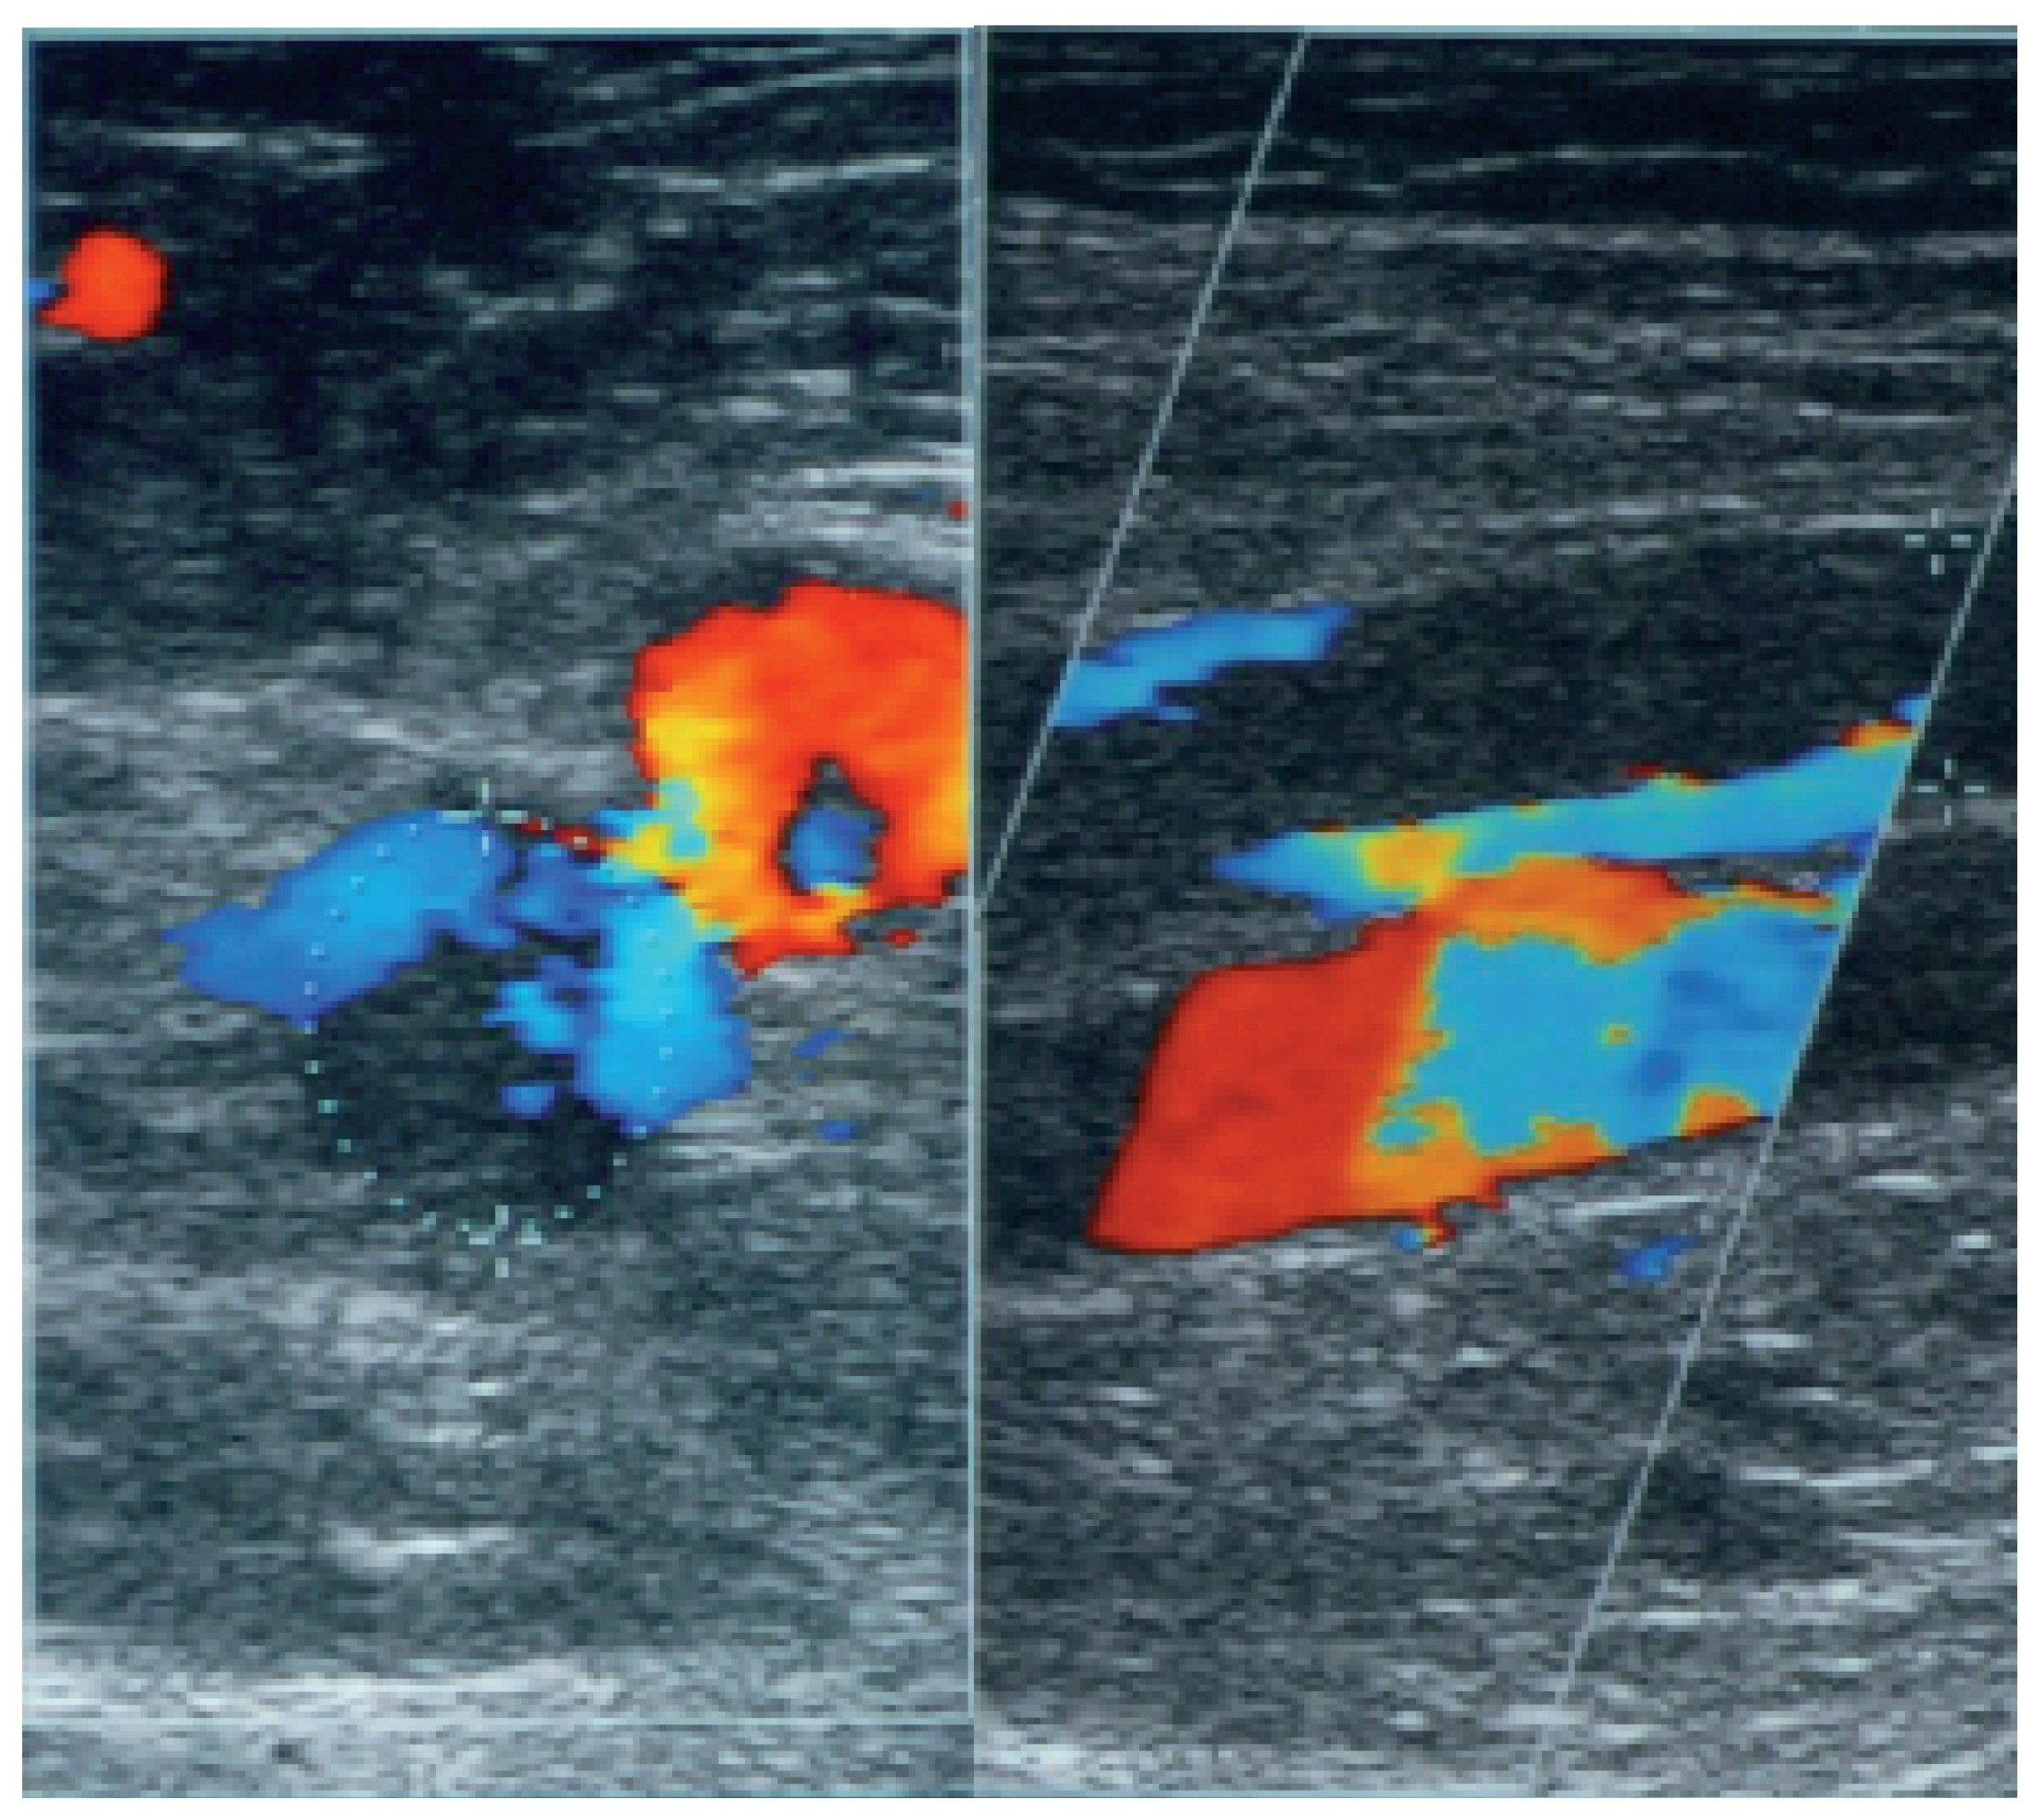

Real-time compression ultrasound and colour coded duplex sonography